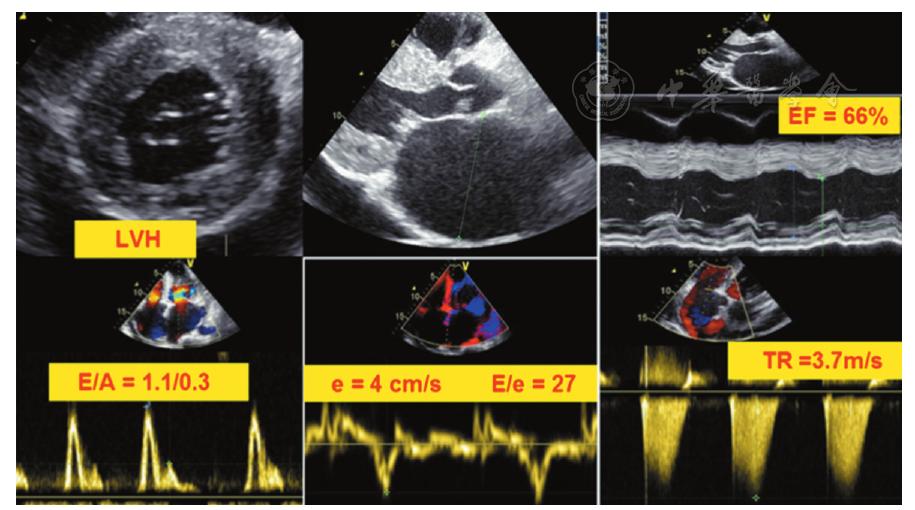

超声心动图

超声心动图解读

二维超声心动图

超声心动图正常值